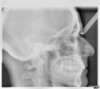

Radios après le traitement